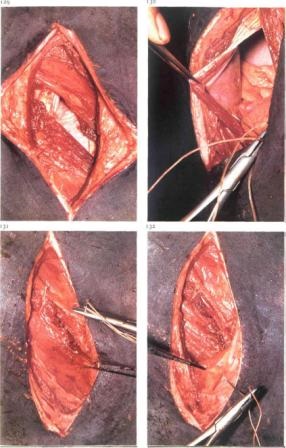

Utilizați cusătură expansiv (metoda Utrecht) folosind o sutură convențională. Cusătura începe la aproximativ 2 cm de la marginea superioară a plăgii.

Suturile se utilizează o metodă în care ansamblul este îngropat într-un țesut inversata. cusătură Următoarea începe la aproximativ 2 cm de la marginea de taiere si este directionat la un unghi de 45 °.

Pe de alta parte este același, dar introduce o oarecare distanță înapoi de la apariția cusătura anterioare. Este important ca fiecare cusătură este strâns după ce a fost introdus. Această inversare previne scurgerea și lasă un impact minim sutura. Înainte de a închide tetraciclină utero ipotecare.

Este necesar să se injecteze oxitocină intramuscular, antibioticele sistemice. Placenta vine de obicei după 4 ore. Retentio posibil, dar puțin probabil.